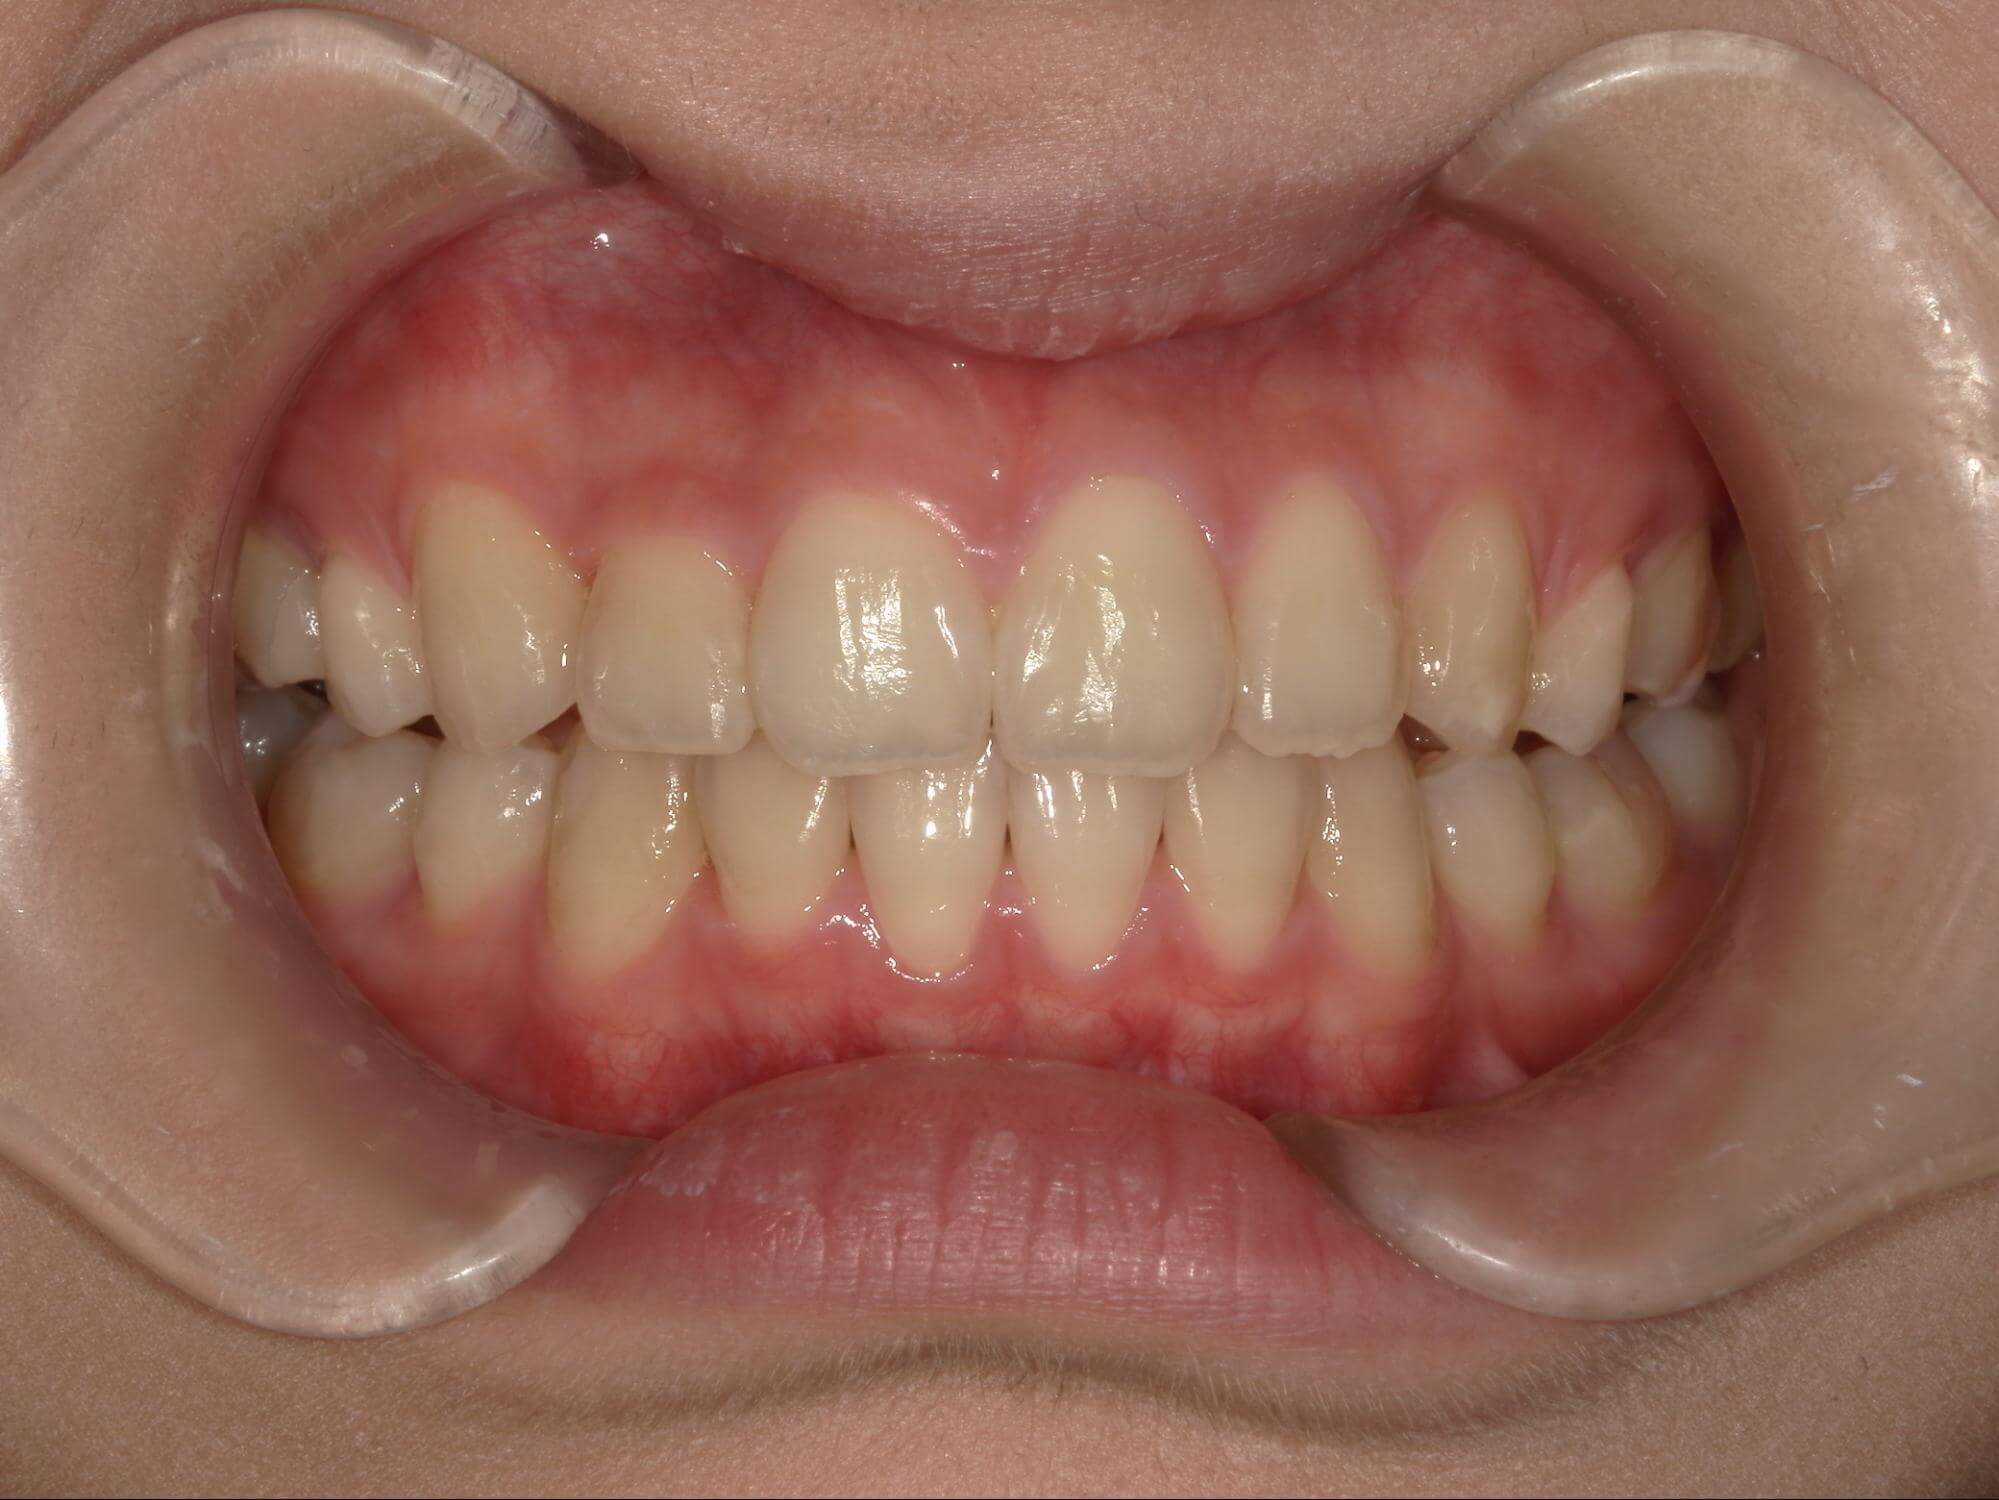

| 年齢・性別 | 21歳 |

|---|---|

| 主訴 | 叢生が気になる・前歯に埋伏歯がある |

| 治療期間・回数 | 6ヶ月 |

| 費用 | 935,000円 |

| 上顎の左側3番が埋伏していたため、上顎左右の3番および親知らずを抜歯し、矯正治療を行いました。 治療開始からおよそ6ヶ月で歯列が整い、審美的にも機能的にも良好な結果が得られた症例です。 |